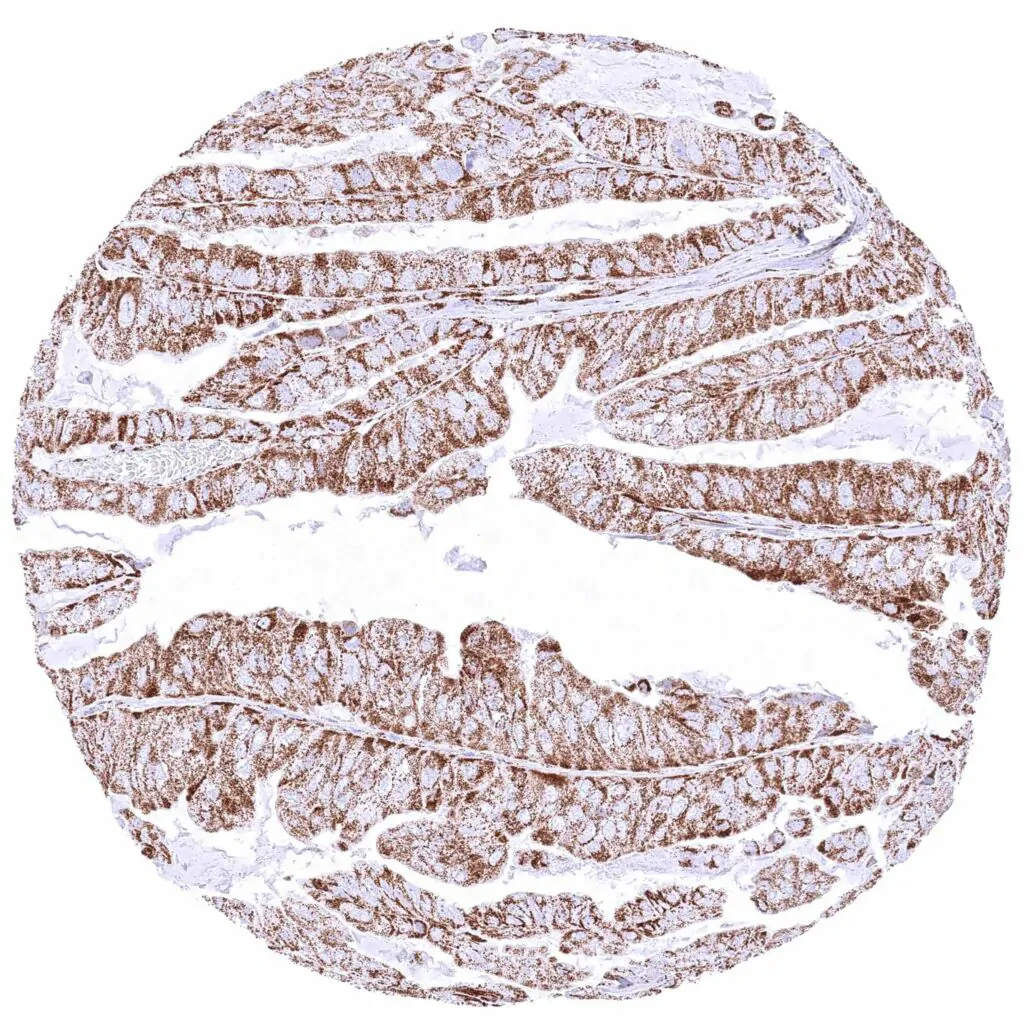

Stomach – Gastric adenocarcinoma (intestinal type) with strong cytoplasmic ATP5J staining of all tumor cells.